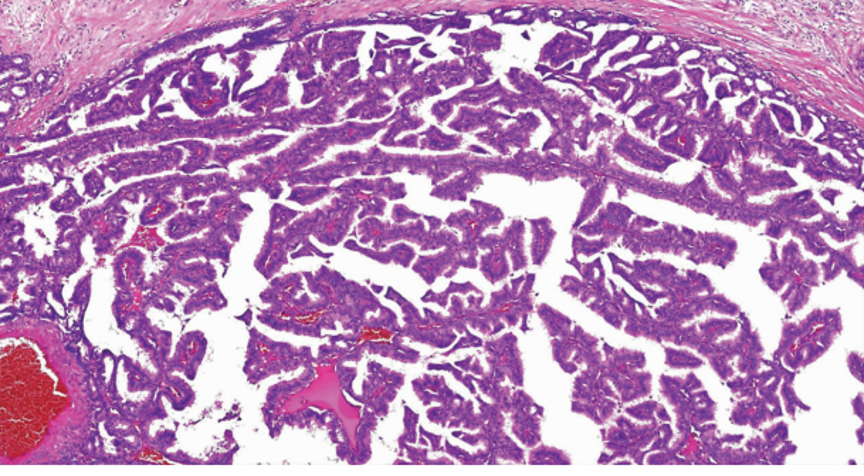

结构特点:轮廓清楚的实性结节纤细的血管轴心。

纤细的脉管轴心

纤细的血管轴心周围细胞呈栅栏状排列

SPC+富于细胞的黏液癌

浸润性SPC